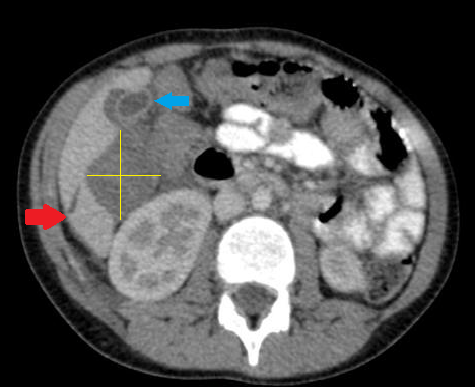

Bu kesitte 12 yaşında appendektomi yapılan bir hastada 1 gün sonra gelişen sağ üst kadran ağrısı nedeniyle çekilen tomografi görüntüsünü görüyoruz. Kırmızı okla işaretli bölge karaciğerde laserasyon alanını, sarı çizgilerle işaretli bölgede kapsülün yırtılması nedeniyle oluşan hematom imajını gösteriyor. Safra kesesi mavi okla işaretli. Safra kesesinin etrafında da hematom devam ediyor. Operasyon sırasında karaciğer laserasyonuna bağlı gelişen hematom konservatif olarak tedavi edilmiş.